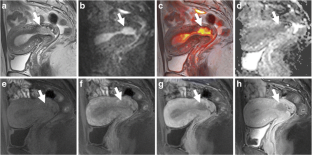

Fig. 1